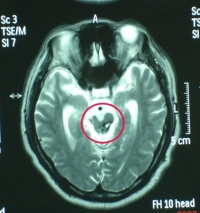

右侧颞叶脑挫裂伤

CT扫描[编辑 | 编辑源代码]

对脑挫裂伤与脑震荡可以作出明确的鉴别诊断,并能清楚地显示脑挫裂伤的部位、程度和有无继发损害,如出血和水肿情况。同时,可根据脑室和脑池的大小、形态和移位的情况间接估计颅内压的高低。尤为重要的是,对一些不典型的病例,可以通过定期CT扫描,动态地观察脑水肿的演变或迟发性血肿的发生。近年来,在有此设备的医院CT已作为急性头伤的常规检查,因为单靠伤史和查体难以作出超早期诊断。Stein等(1990)指出在GCS13~15危害较小的轻型头

右额颞叶脑挫裂伤合并蛛网膜出血

伤中,首次CT的阳性发现率竟占18%,并有5%需行手术治疗,强调早期CT检查的必要性。